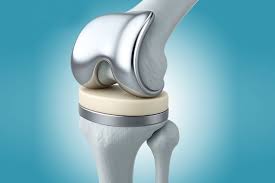

Robotic knee replacement in Narsinghpur Robotic knee replacement in Narsinghpur is an advanced orthopedic procedure that uses robotic-assisted technology to improve the precision and accuracy of knee joint replacement...

Robotic knee replacement in Shahdol Robotic knee replacement in Shahdol is transforming joint care for patients dealing with severe knee pain, stiffness, and reduced mobility. This advanced procedure combines...

Robotic knee replacement in Umaria Robotic knee replacement in Umaria is an advanced orthopedic solution designed to treat severe knee damage with enhanced precision and better outcomes. Moreover, it...